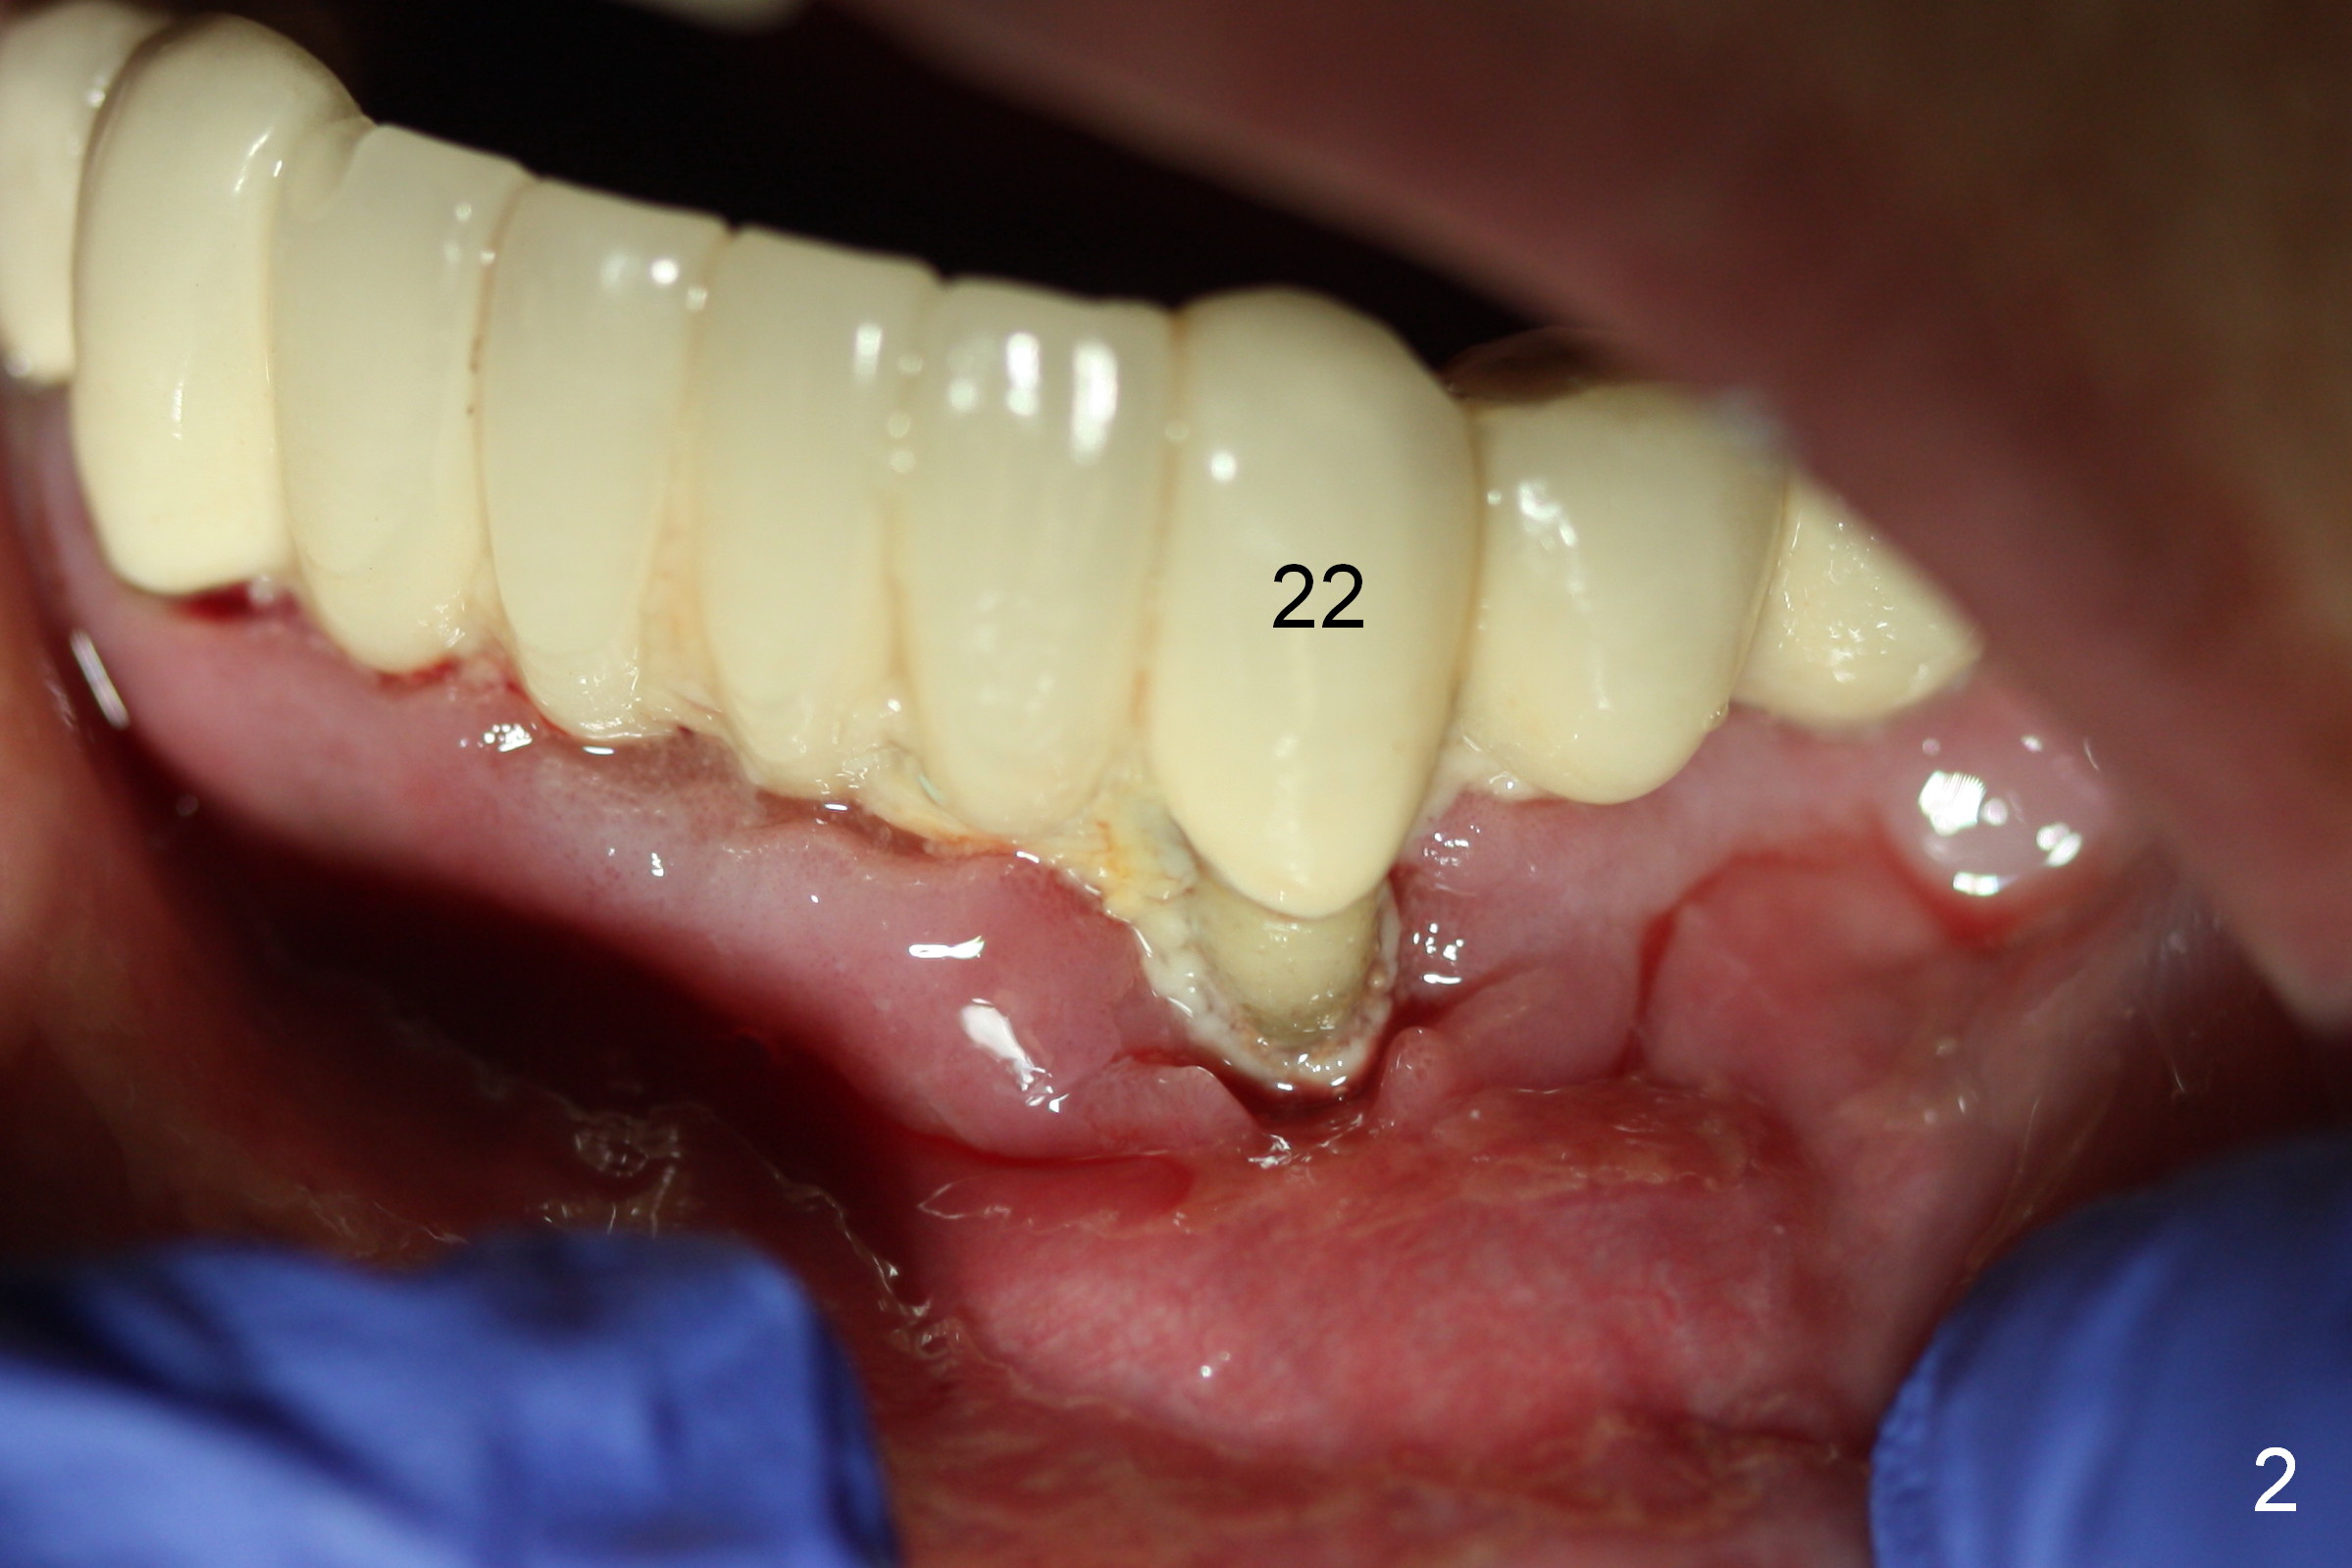

A 72-year-old woman has severe pain associated with one of three abutments of a long-spanned bridge (Fig.1,2: #22). The lingual calculus is extremely large (Fig.3 C). When the bridge is sectioned between #26 and 27, the tooth #22 is easily separated from the socket (Fig.4). In fact, the large supragingival calculus causes hemorrhagic indentation in the lingual vestibule (Fig.5,6: I). Due to finance, socket preservation is done at #22 with 6-month collagen membrane buccally and .5-1.5 mm allograft and collagen plug (Fig.6 *).